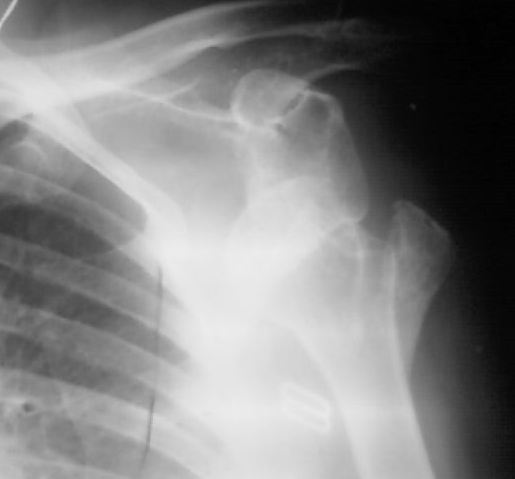

На рентгенснимке левого плеча в передне-задней проекции полный вывих плеча с отрывом большого бугорка. Пальпаторно головка под клювовидным отростком лопатки. Со слов девушки, 6 месяцев назад получила травму, упала на область левого плеча с высоты примерно 2 метров. За медицинской помощью обратилась только сейчас (не знаю почему столько времени находилась без медицинской помощи....почему то пациентка не хочет об этом говорить). Сейчас больше всего беспокоят боли, чем ограничение движений, хотя ограничение движений в левом плечевом суставе существенное.Неврологических и сосудистых нарушений в левой руке нет